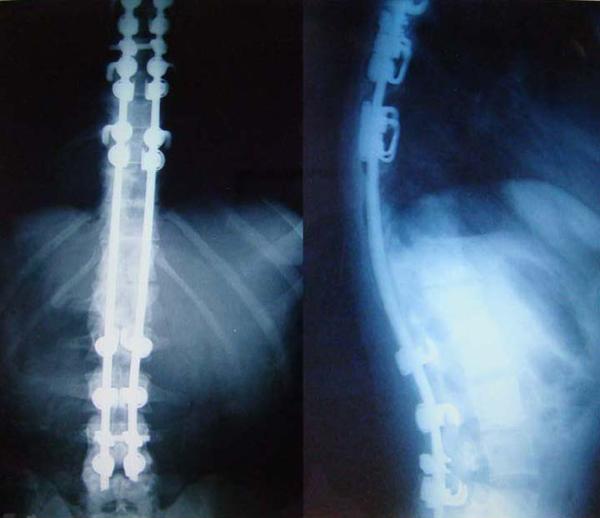

孤立性胸长神经麻痹——脊柱前路手术的一种罕见并发症:病例报告

Isolated long thoracic nerve paralysis - a rare complication of anterior spinal surgery: a case report.

We present the case of a 23-year-old woman who sustained isolated long thoracic nerve palsy during anterior spinal surgery which caused external compressive force on the nerve.

我们报告一例23岁女性病例,该患者在脊柱前路手术期间发生孤立性胸长神经麻痹,手术对神经造成了外部压迫。